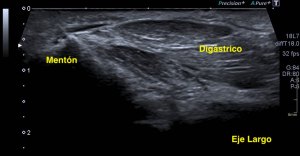

De presentación rara, su aspecto es típico de un músculo, justo encima del canal del cubital, donde normalmente no tiene que haber nada…Mira la normalidad de la anatomía ecográfica del canal cubital:

Para localizar esta ecoarquitectura tienes que trazar una línea imaginaria entre el olécranon y la epitróclea, visible por la orografía del codo y palpables, así que no tiene pérdida. Vas a ver el nervio cubital en un corte axial. Redondo, en forma de panel de abeja, observa la parte superior de la imagen ecográfica donde no existe nada por encima del nervio, justo en esa línea imaginaria que te he pedido que uses para conseguir esta imagen…